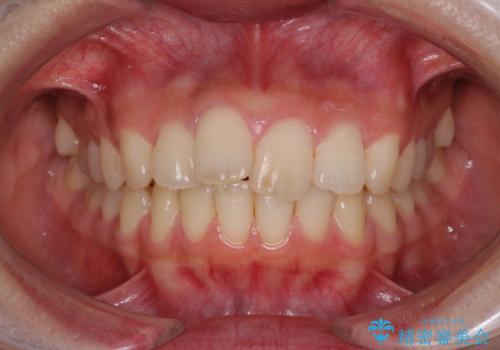

抜歯矯正の後戻りが気になる インビザライン・ライトによる矯正治療